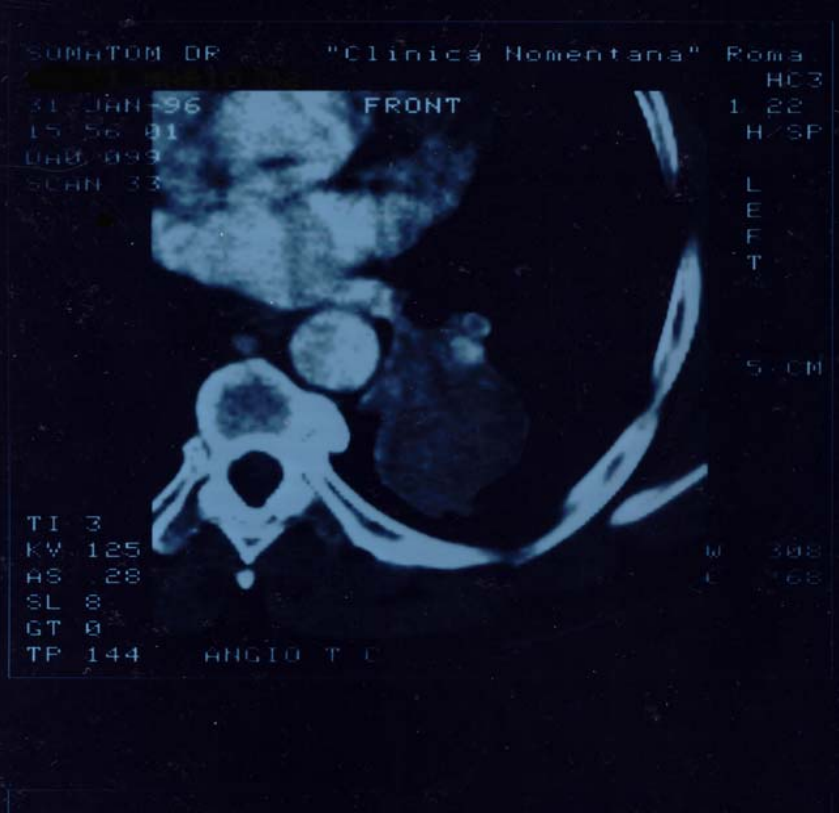

Figure4